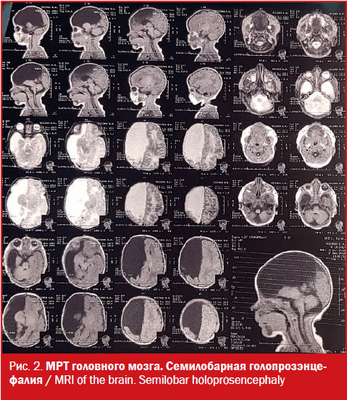

МРТ: на серии Т1- и Т2-взвешенных томограмм в сагиттальной и аксиальной проекции получено изображение супратенториальных структур головного мозга. Правые лобная, теменная и частично височная доли (кроме гиппокампа), мозолистое тело и прозрачная перегородка отсутствуют, нижний червь мозжечка гипопластичный. Правый зрительный бугор увеличен в размерах, визуализируется частично правая затылочная доля. Левое полушарие большого мозга, полушария мозжечка и ствол сформированы правильно. Ретенции желудочковой системы нет. Признаков объемного воздействия не отмечено. Базальные цистерны открыты. В заключении отмечено, что полученные данные могут соответствовать МР-картине семилобарной голопрозэнцефалии (рис. 2).